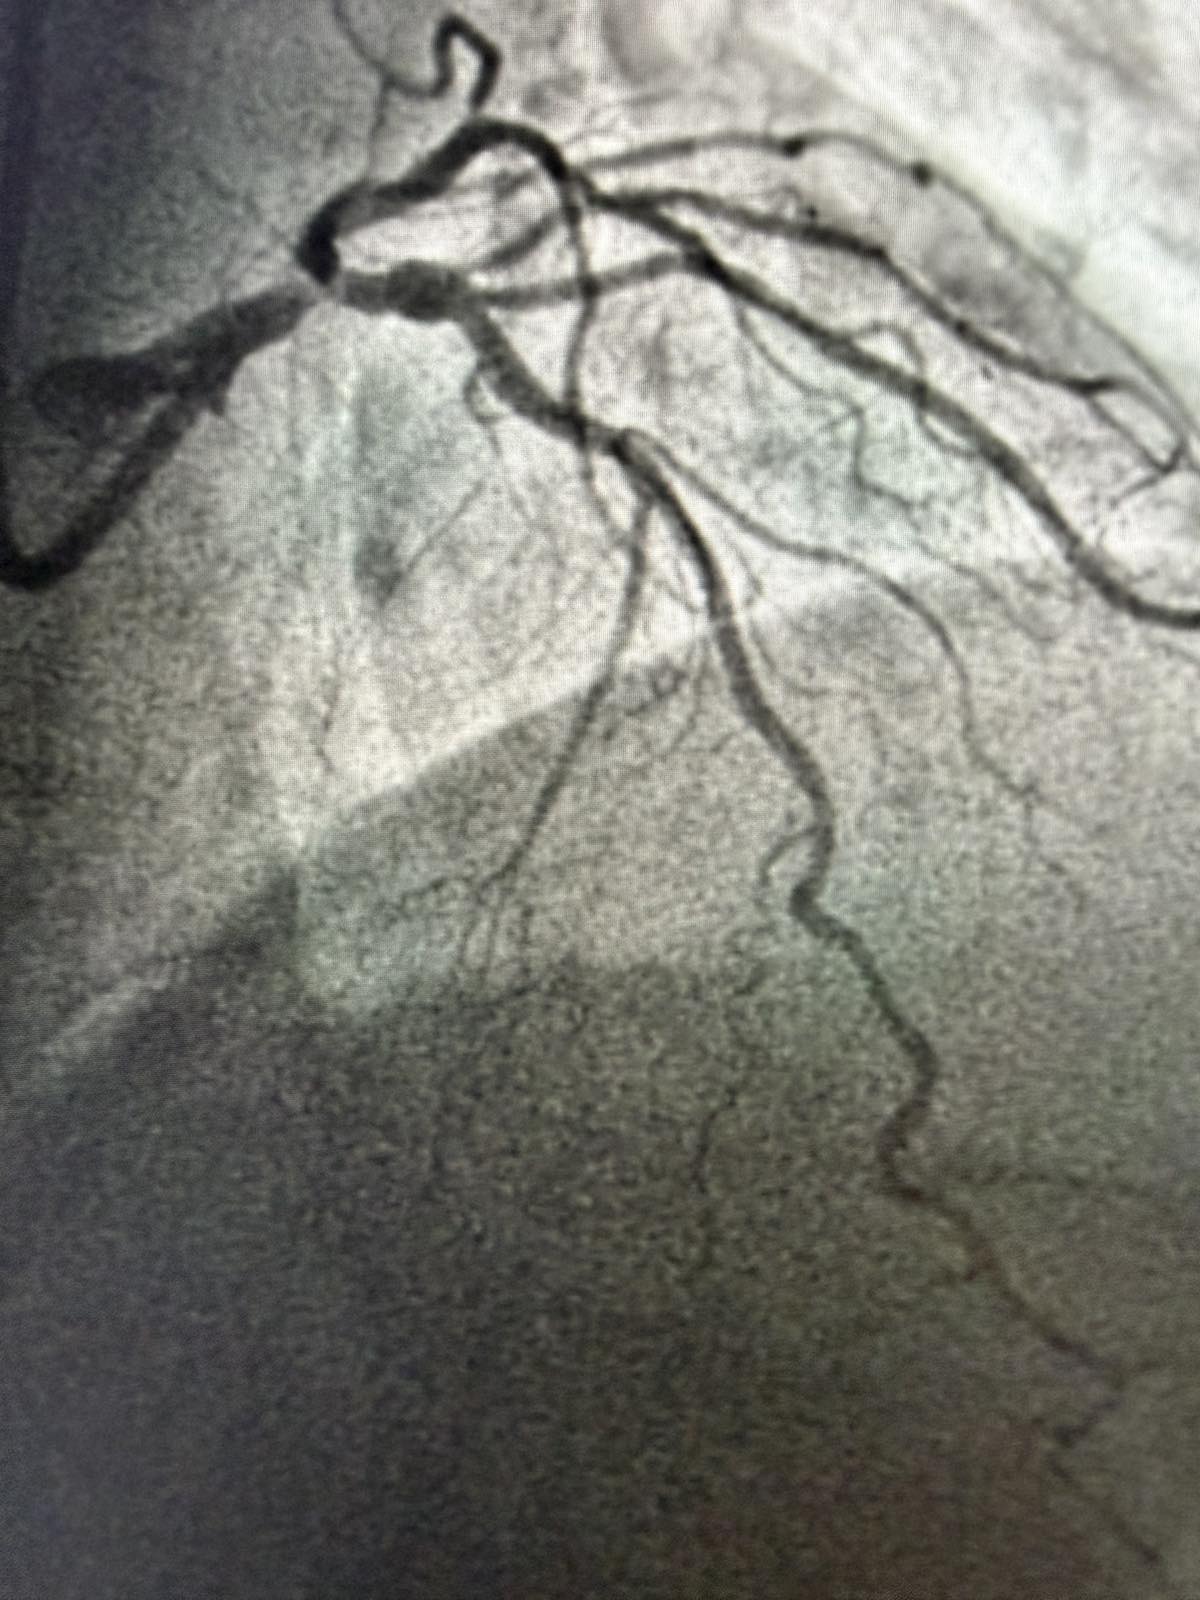

Tokom dva dana u angio sali izvedene su i izuzetno složene intervencije na koronarnim arterijama srca, uključujući perkutane intervencije na hronično - potpuno zapušenim krvnim sudovima srca i intervencije na tzv. glavnom stablu (left main) koja je glavna artrija srca i čije liječenje takođe spada u veoma rizične zahvate u interventnoj kardiologiji.

Kod pacijenta D.B iz Bratunca, koji je prije dvije godine prebolio infarkt i imao hroničnu potpunu zapušenost jedne arterije, urađena je perkutana koronarna intervencija kojom je arterija u potpunosti otvorena. Iako ove procedure imaju niži procenat uspjeha i zahtijevaju veliko iskustvo operatera, uspješno je izvedena. Dan nakon intervencije pacijent dobrog opšteg stanja otpušta se na kućno liječenje.

Još jedan slučaj koji izdvajamo kao posebno složen je bio kod pacijenta O.M (81), kod kojeg je dijagnostikovana teška trosudovna koronarna bolest.

„Pacijent je imao simptome angine pectoris. Nakon urađene koronarografije verifikovana je teška trosudovna koronarna bolest, gdje su bolesne bile desna koronarna arterija, dok je na lijevoj strani kritično mjesto bilo na glavnom stablu  odakle ide račvanje u dvije grane. Takvi pacijenti uglavnom završavaju na kardiohirurškom konzilijumu i na operaciji bajpasevima. Međutim, odluka konzilijuma u Banjaluci je bila da se, zbog godina života pacijenta,  radi perkutana intervencija na desnoj i lijevoj koronarnoj arteriji uključujući glavno stablo.Takve procedure zahtijevaju da se rade sa kontrolom imidžinga, savremene intravaskularne dijagnostike (IVUS), što smo mi i uradili. To dodatno povećava bezbijednost i preciznost zahvata. Procedura je trajala svega 45 minuta, a pacijent je već narednog dana otpušten kući“, izjavio je dr Janjičić.